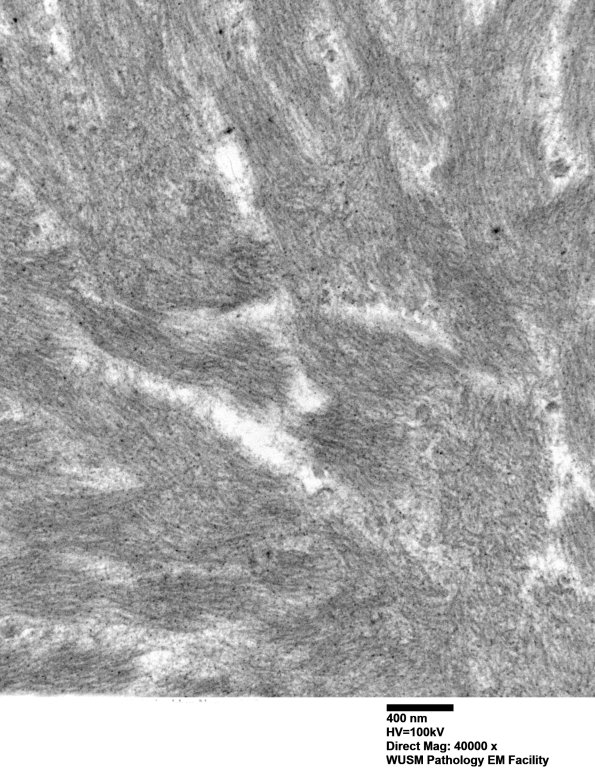

Amyloid fibrils are unbranched and approximately 10nm in width. (electron micrographs)